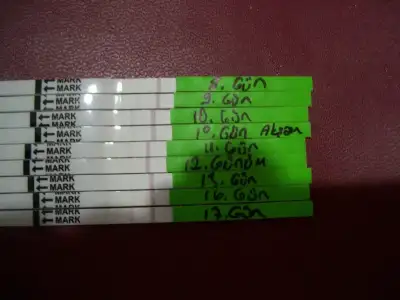

merhaba arkadaşlar uzun bi süredir giremedim işlerimin yoğunluğundan dolayı. Coretest almıştım ya, normalde benim adetim düzensiz oluyordu yani bir ay 28 gün bir ay 32 gün bir ay 30 gün sürüyor döngüm değişiyor. ben adetimin 11. günü başladım testi yapmaya, 2 saat öncesinde fazla sıvı tüketmiyorum her gün aynı saatte yapıyrum. 11. gün tek çigi çıktı, 12. gün de tek çizgiçıktı (yani slik dahi çıkmadı 2. çizgi) 13. gün control çizgisine göre daha silik bir çizgi çıktı testte en az aynı koyulukta ya da daha koyu çıkar diyordu ama ben abşka bir yerde her vücuttaki LH homonunun farklı seviylerde üretilebildiğii okumuştum belki benimki az üretiyordur diyerek 13. günü değerlendirdik eşimle (1 gün ara verdik 2. gün yine çalıştık) 14. gün ben yine denedim testi bir önceki güne göre bu sefer daha ince 2. çizgi çıktı. dün yaptığımda yani 15. gün yeniden tek çizgiye düşmüştü. yani doğru günü yakaladığımıza inanıyorum zaten 14. gün gündüz ince ince kasık ağrısı çektim muhtelemelen yumurta çatlıyordu